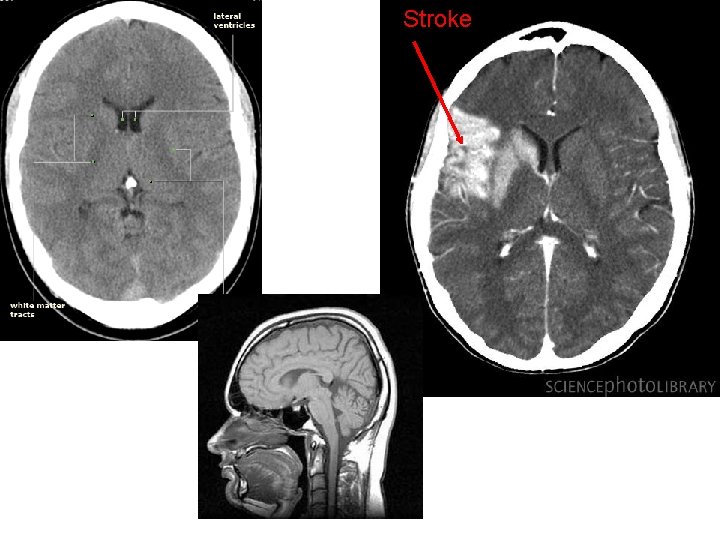

CT • What do we use the scan for? – Allows us to see soft tissue of the brain • Structure changes to do to damage or tumor • Strengths/limitations – Strengths: Great at see structural changes • Brain tumor/damage – Limitations: does not show brain activity • Research support – Ogden (2005)

Stroke

Ogden (2005) • Method: Case Study • AIM: study the impact of a brain tumor on hemineglect – Hemineglect: brain damage causes inattention to the opposite side of space • Procedure – Neurological assessments: • Scan the brain (CT) • Draw pictures, read • Implications – Patients are aware of the neglect (jokes, justifications) but a willing neglect by half the brain Tumor